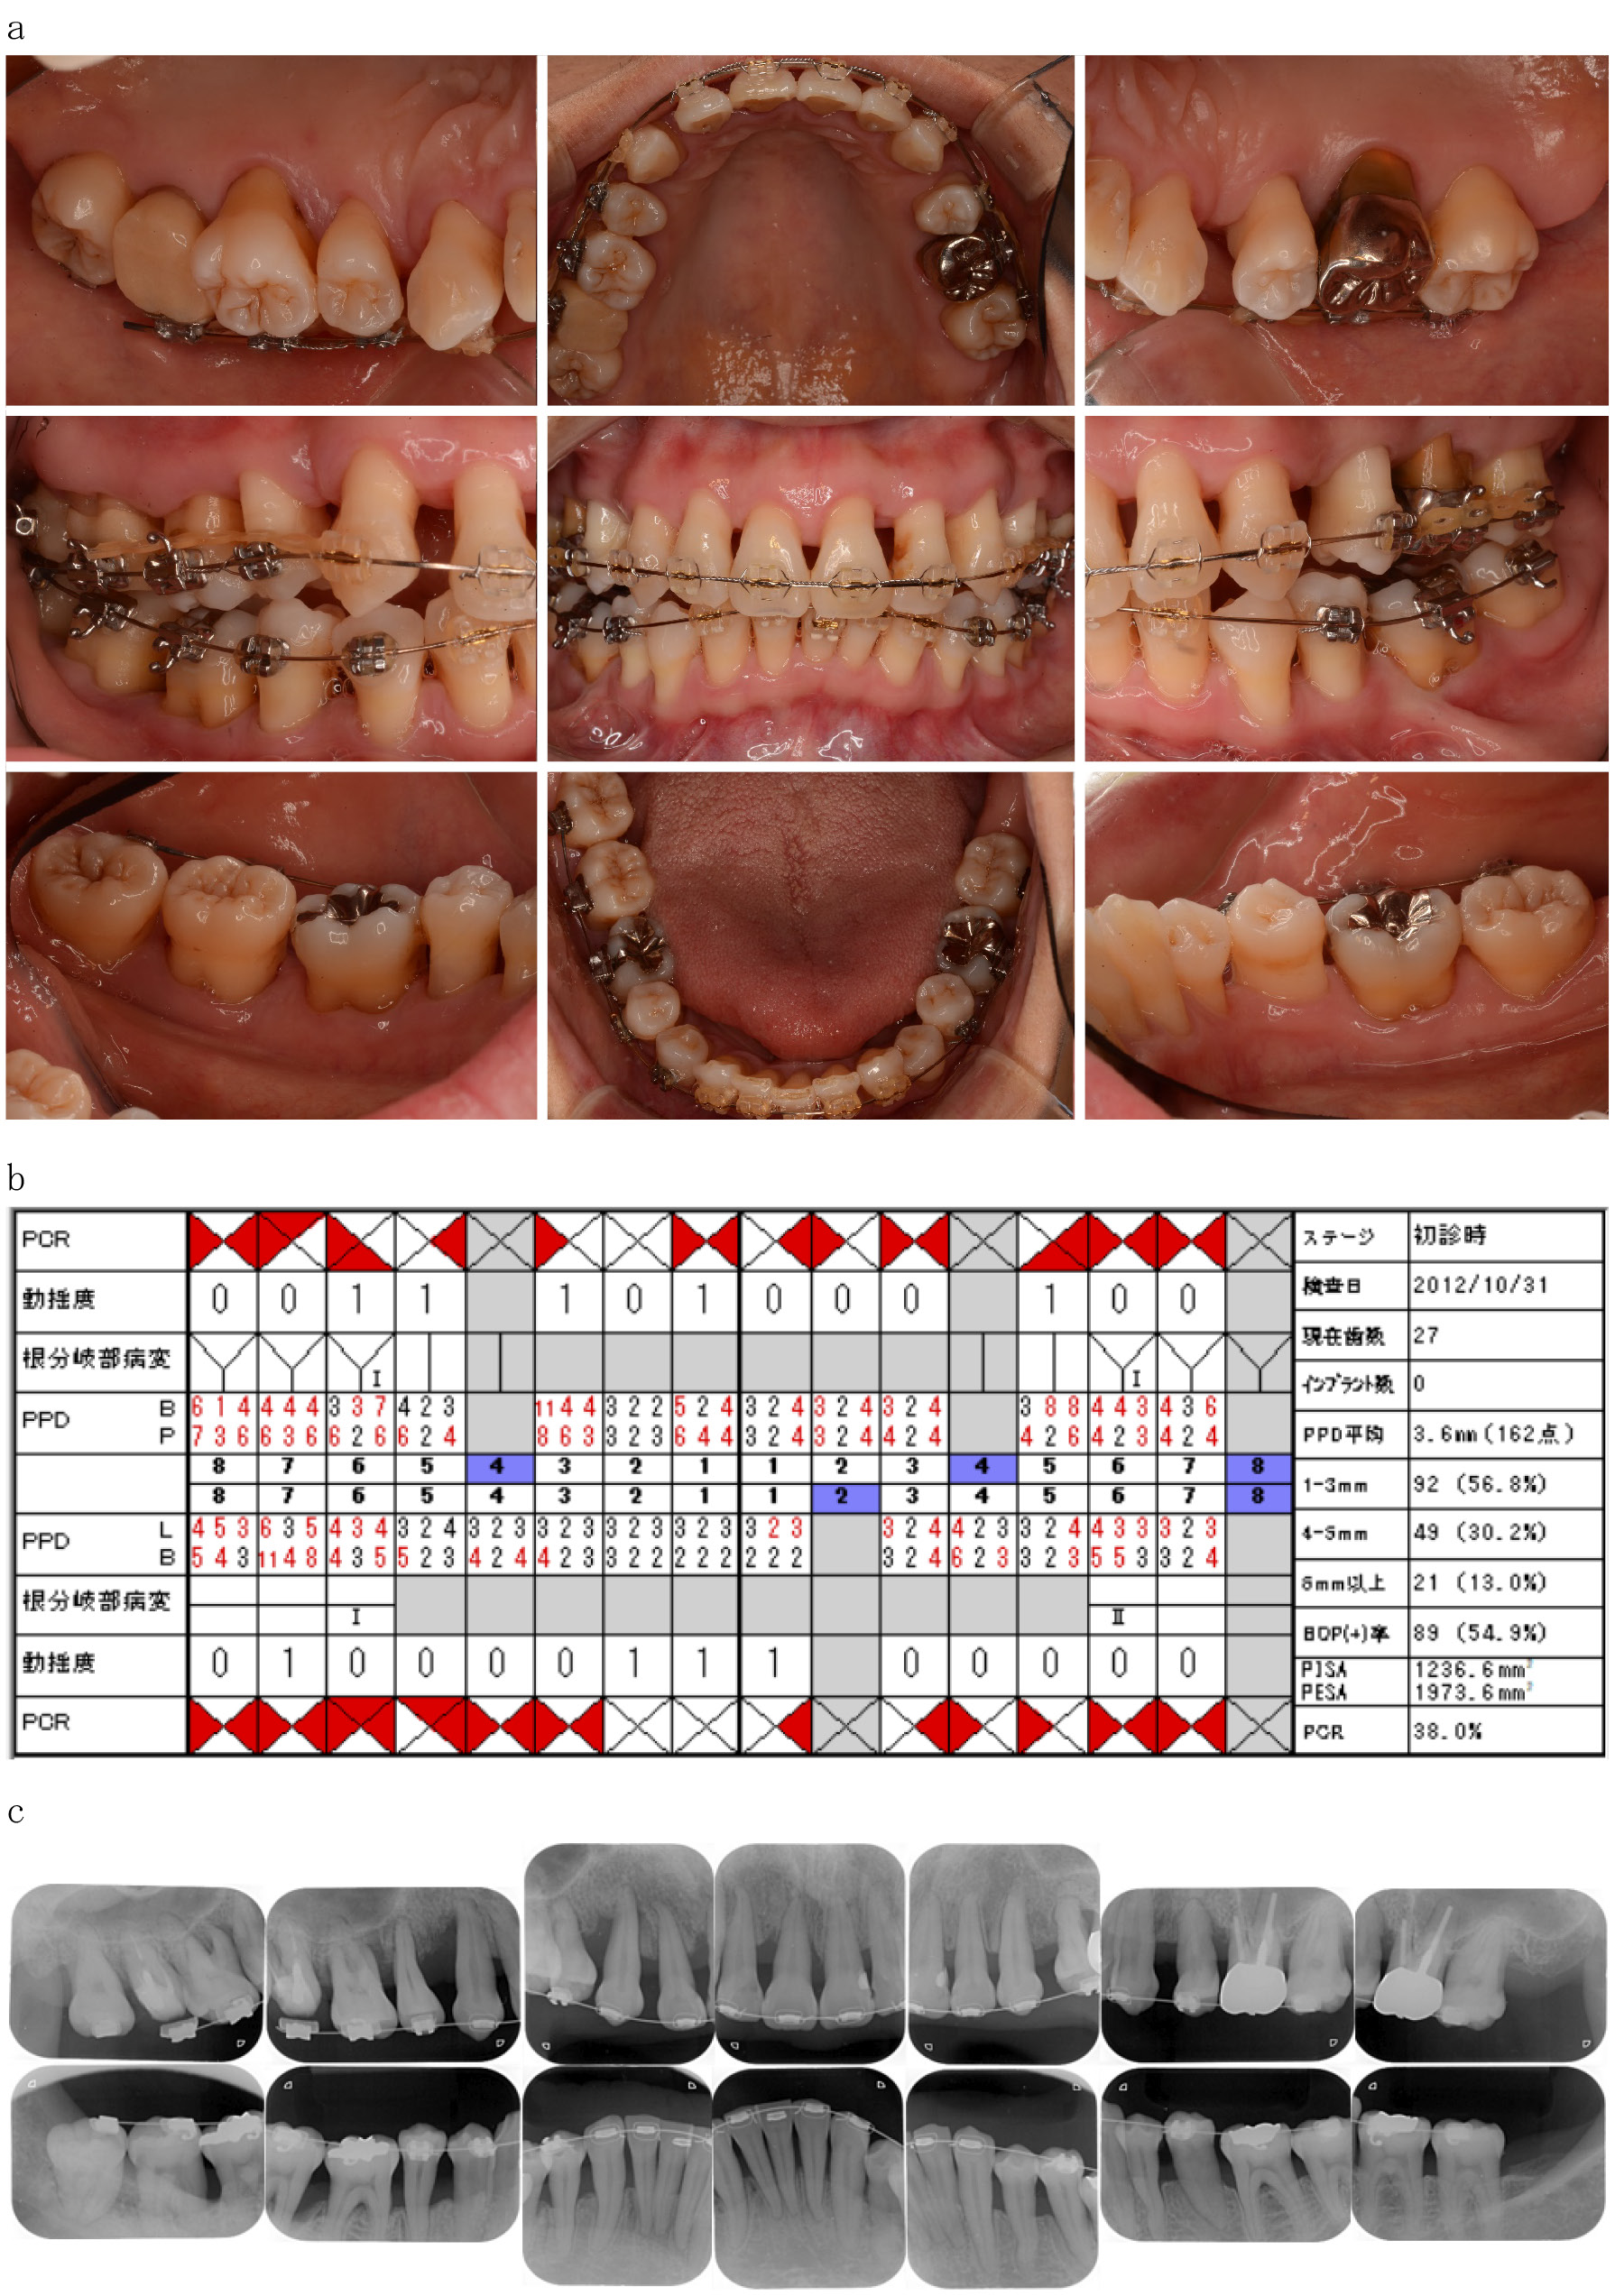

1. 初診時現症1)口腔内所見:歯肉は,浮腫性で全顎に発赤,腫脹を認めた。歯肉退縮は,全顎CEJから3~5 mm程度認め,歯間乳頭は大きく退縮していた。歯には矯正用ブラケットが装着され咬合は左右大臼歯が1か所のみの咬合接触を認めた(図1a)。

2)歯周組織検査結果:4 mm以上のProbing depth(PD)の割合は43.2%,Bleeding on Probing(BOP)は54.9%,O'Leary plaque control record(PCR)は38.0%,Periodontal inflamed surface area(PISA)の値は1236.6 mm2認められた。動揺度は16,15,13,11,25,31,41,42,47に1度,根分岐部病変は,16近心,26遠心,46頬側に1度,36に2度認められた(図1b)。

3)エックス線写真所見:全顎にCEJから6 mm以上の著明な水平的吸収を認め,11近遠心部,13遠心部,25遠心部,47近心部に垂直性骨欠損を認めた。17,26は根管充填されており根尖病変は認められない。36,46の根分岐部には,わずかにエックス線透過像を認めた(図1c)。

初診時の臨床資料(2012年10月)

a 口腔内写真

b 歯周組織検査結果

c エックス線写真